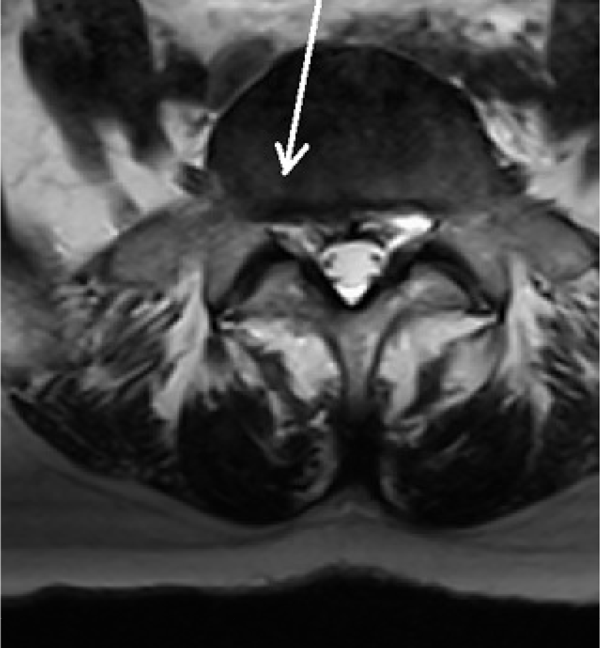

Die folgenden MRT Bilder stammen von einem Patienten mit Bandscheibenvorfall L5/S1. Der Patient ist vorher mehrere Monate arbeitsunfähig gewesen und wurde mit diversen konventionellen Verfahren erfolglos behandelt. Als nächster Schritt wäre eine OP angestanden, die mit der SpineMED® Therapie verhindert werden konnte. Sollten Sie Fragen haben, zögern Sie nicht uns zu kontaktieren, wir bemühen uns um einen Zeitnahen Termin für Sie, und beantworten alle Fragen gerne.

Nach Spinemed